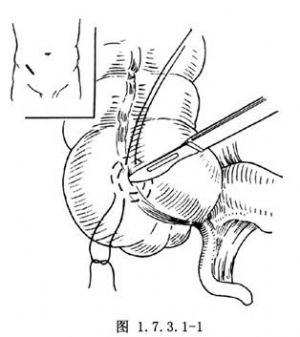

1.右下腹部斜切口,进腹后,提出膨胀盲肠,周围用盐水纱布保护。用不吸收线在盲肠前结肠带处做两个同心荷包缝合,彼此相距1cm。在荷包缝合中央做一小切口(图1.7.3.1-1)。